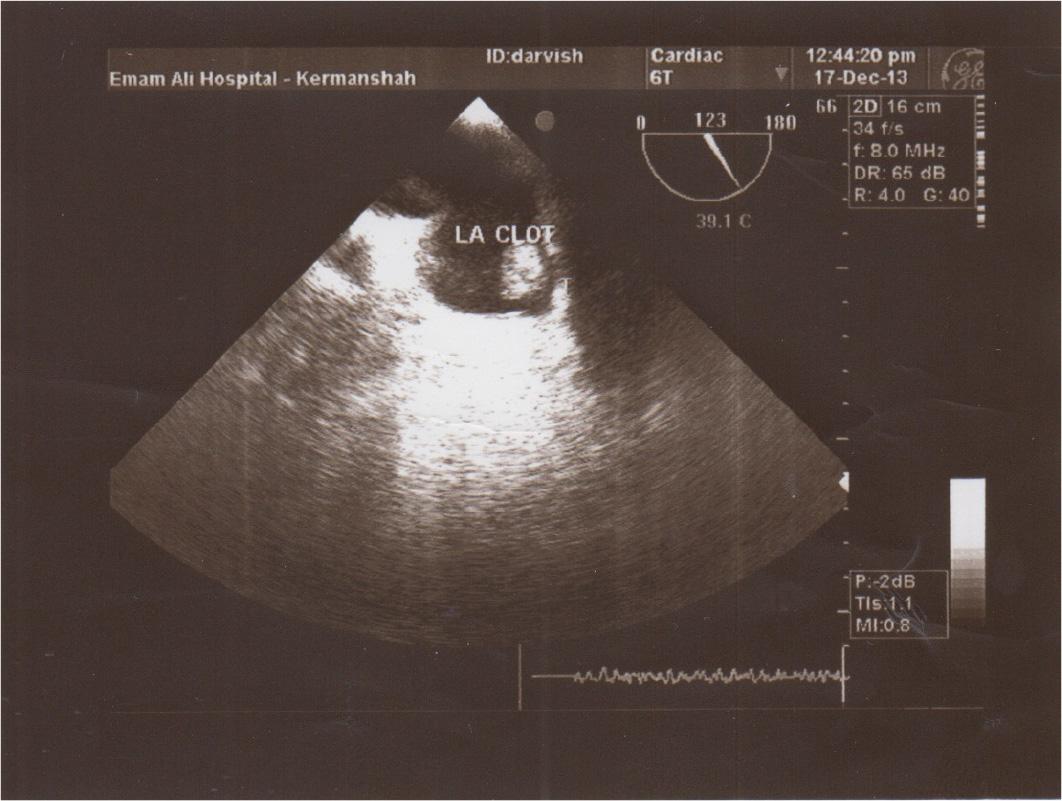

Figure 2

Left atrial circumferential clot.